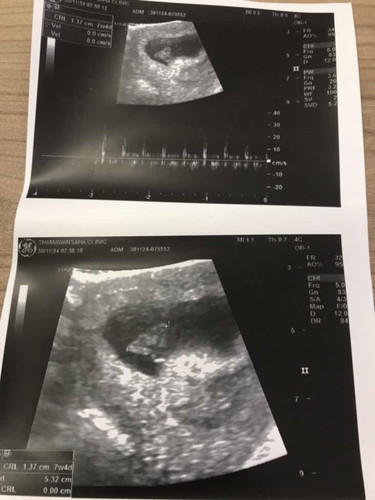

พึ่งไปซาวด์มาวันนี้ค่ะ 7w 4d แบบนี้คือน้องปกติไหมคะแม่ๆ

สอบถามเพื่อความแน่ใจค่ะ